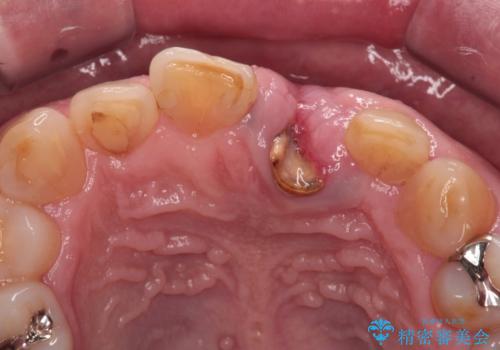

歯茎に溝が 大きく欠損した前歯のインプラント補綴治療

- 歯が朽ちてしまい、歯茎に大きな溝ができていることを気にして来院された患者様です。

インプラント治療を希望されておりましたが、軟組織の欠損が非常に大きいため、骨の回復を待ちながら歯肉の形態を整えていくこととしました。